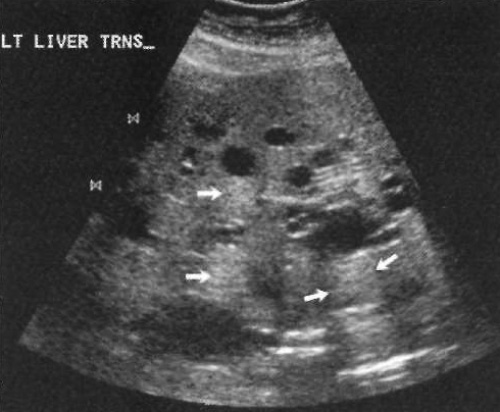

Многие пациенты не предъявляют жалоб до тех пор, пока не возникает боль из-за кровоизлияния в полость кисты. Ультразвуковая картина при поликистозе печени аналогична простым кистам – анэхогенные образования с четкими стенками и задним акустическим усилением (фото 7).

Фото 7. Поликистоз печени. По всей площади сечения отмечаются множественные мелкие кистевидные очаги. Стрелками обозначены усиления звука после прохождения кист – задний акустический эффект